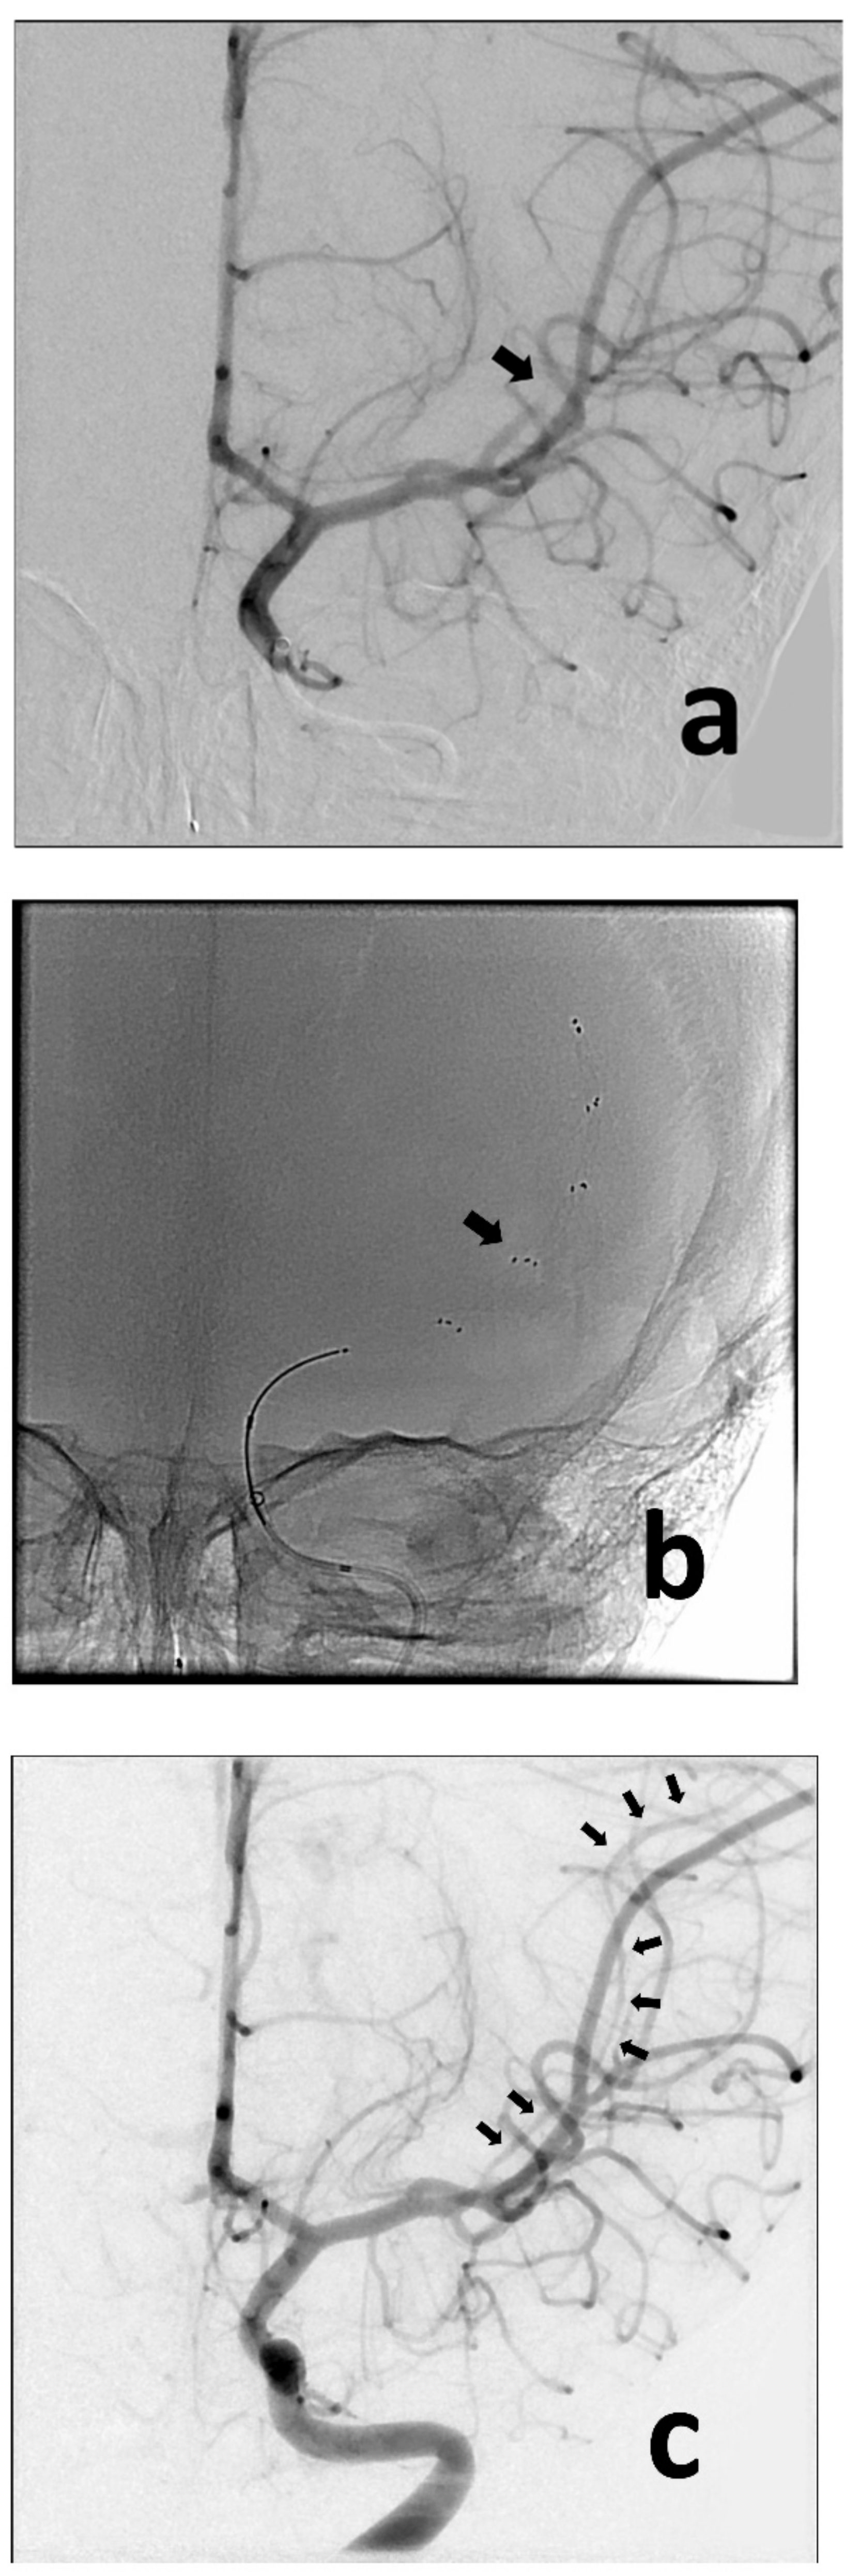

Figure 2.

Anteroposterior angiographic and fluoroscopic views of the thrombectomy procedure. Baseline image confirms occlusion of the MCA (md) (a) (black arrow). The retriever was deployed across the point of occlusion (i.e., normal-to-normal) (b) (black arrow). Following removal of the retriever, the MCA (md) is now visualized (c) (multiple black arrows), despite showing some spasm (typically caused by the device).